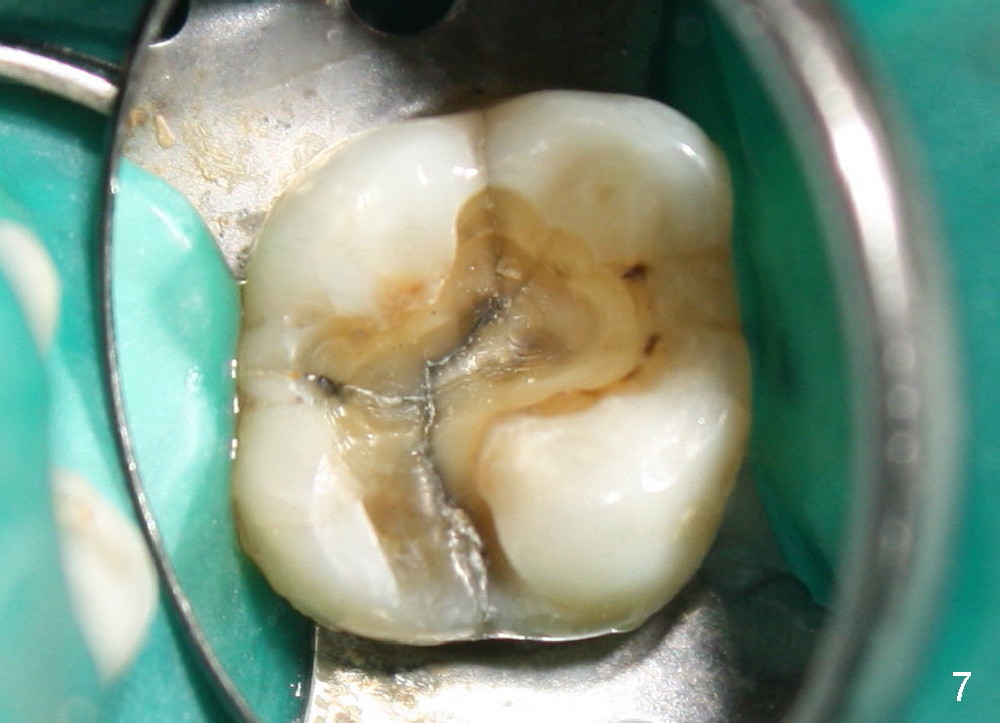

让我们再举例说明证明上颌窦中有骨质:三个月前,四十来岁女士来诊所诊治,左上六不适(图六),咬合面有一个大块银汞充填,周围有裂纹,去除银汞充填后,裂纹延伸至髓腔顶(图七),好像不到髓底,所以尝试根管治疗,但是疼痛没有消失,我们临时决定拔牙立即植牙,但是当时没有足够时间注意上颌窦底板,两眼直盯鄂侧根尖(图六:P),因此最后植牙就植入那么深(图九:I),晚上欣赏自己“杰作”时,才发现上颌窦底板(箭头),虚汗一身:一大节植牙捅进上颌窦,马上打电话给病人,她有些鼻血,但是她还不愿意回来复诊。拔牙后准备在中隔正中植牙,使用骨凿,tap形成植牙窝,后者颊侧骨壁有小面积穿孔,但是上颌窦膜还完整,最后植牙掉入鄂侧牙槽窝(图八;S:中隔;MB:近中颊侧牙槽窝;DB:远中颊侧牙槽窝),植牙很牢,torque>60Ncm。